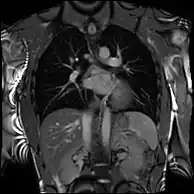

Combined with vasodilator stress, it has a role in detecting and characterizing myocardial ischemia due to disease affecting the epicardial vessels and microvasculature. Late gadolinium enhancement (LGE) and T1 mapping allow infarction and fibrosis to be identified for characterizing cardiomyopathy and assessing viability.[8] Magnetic resonance angiography may be performed with or without contrast medium and is used to assess congenital or acquired abnormalities of the coronary arteries and great vessels.[9]

4D flow CMR

Conventional phase contrast imaging can be extended by applying flow-sensitive gradients in 3 orthogonal planes within a 3D volume throughout the cardiac cycle. Such 4D imaging encodes the velocity of flowing blood at each voxel in the volume enabling fluid dynamics to be visualised using specialist software. Applications are in complex congenital heart disease and for research into cardiovascular flow characteristics - however it is not in routine clinical use due to the complexity of post-processing and relatively long acquisition times.[26]